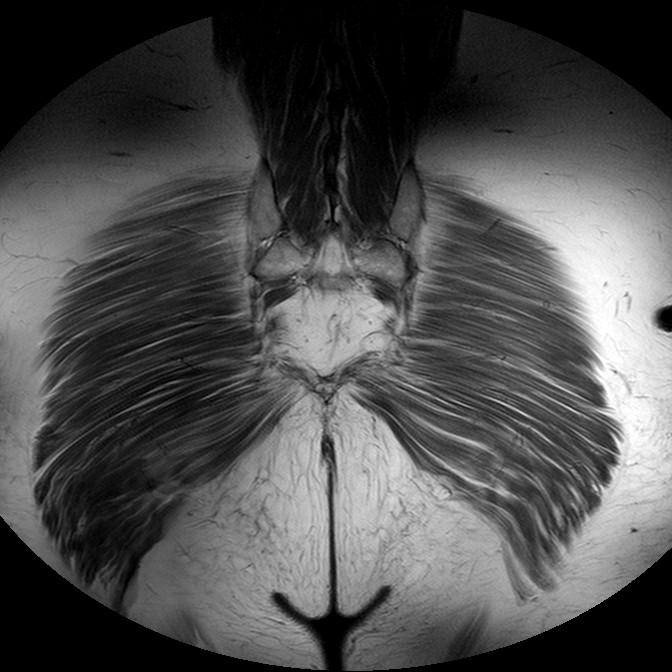

Esami: RMN BACINO

T1w TSE

Evidenti e simmetriche alterazioni osteofitosiche in regione coxo femorale con riduzione delle rime articolari. Degenerazione completa del cercine glenoideo. Non attuali segni di versamento articolare. Non segni di edema osseo che escludono attuale algodistrofia od osteonecrosi. Lieve e simmetrica riduzione del trofismo della muscolatura glutea.